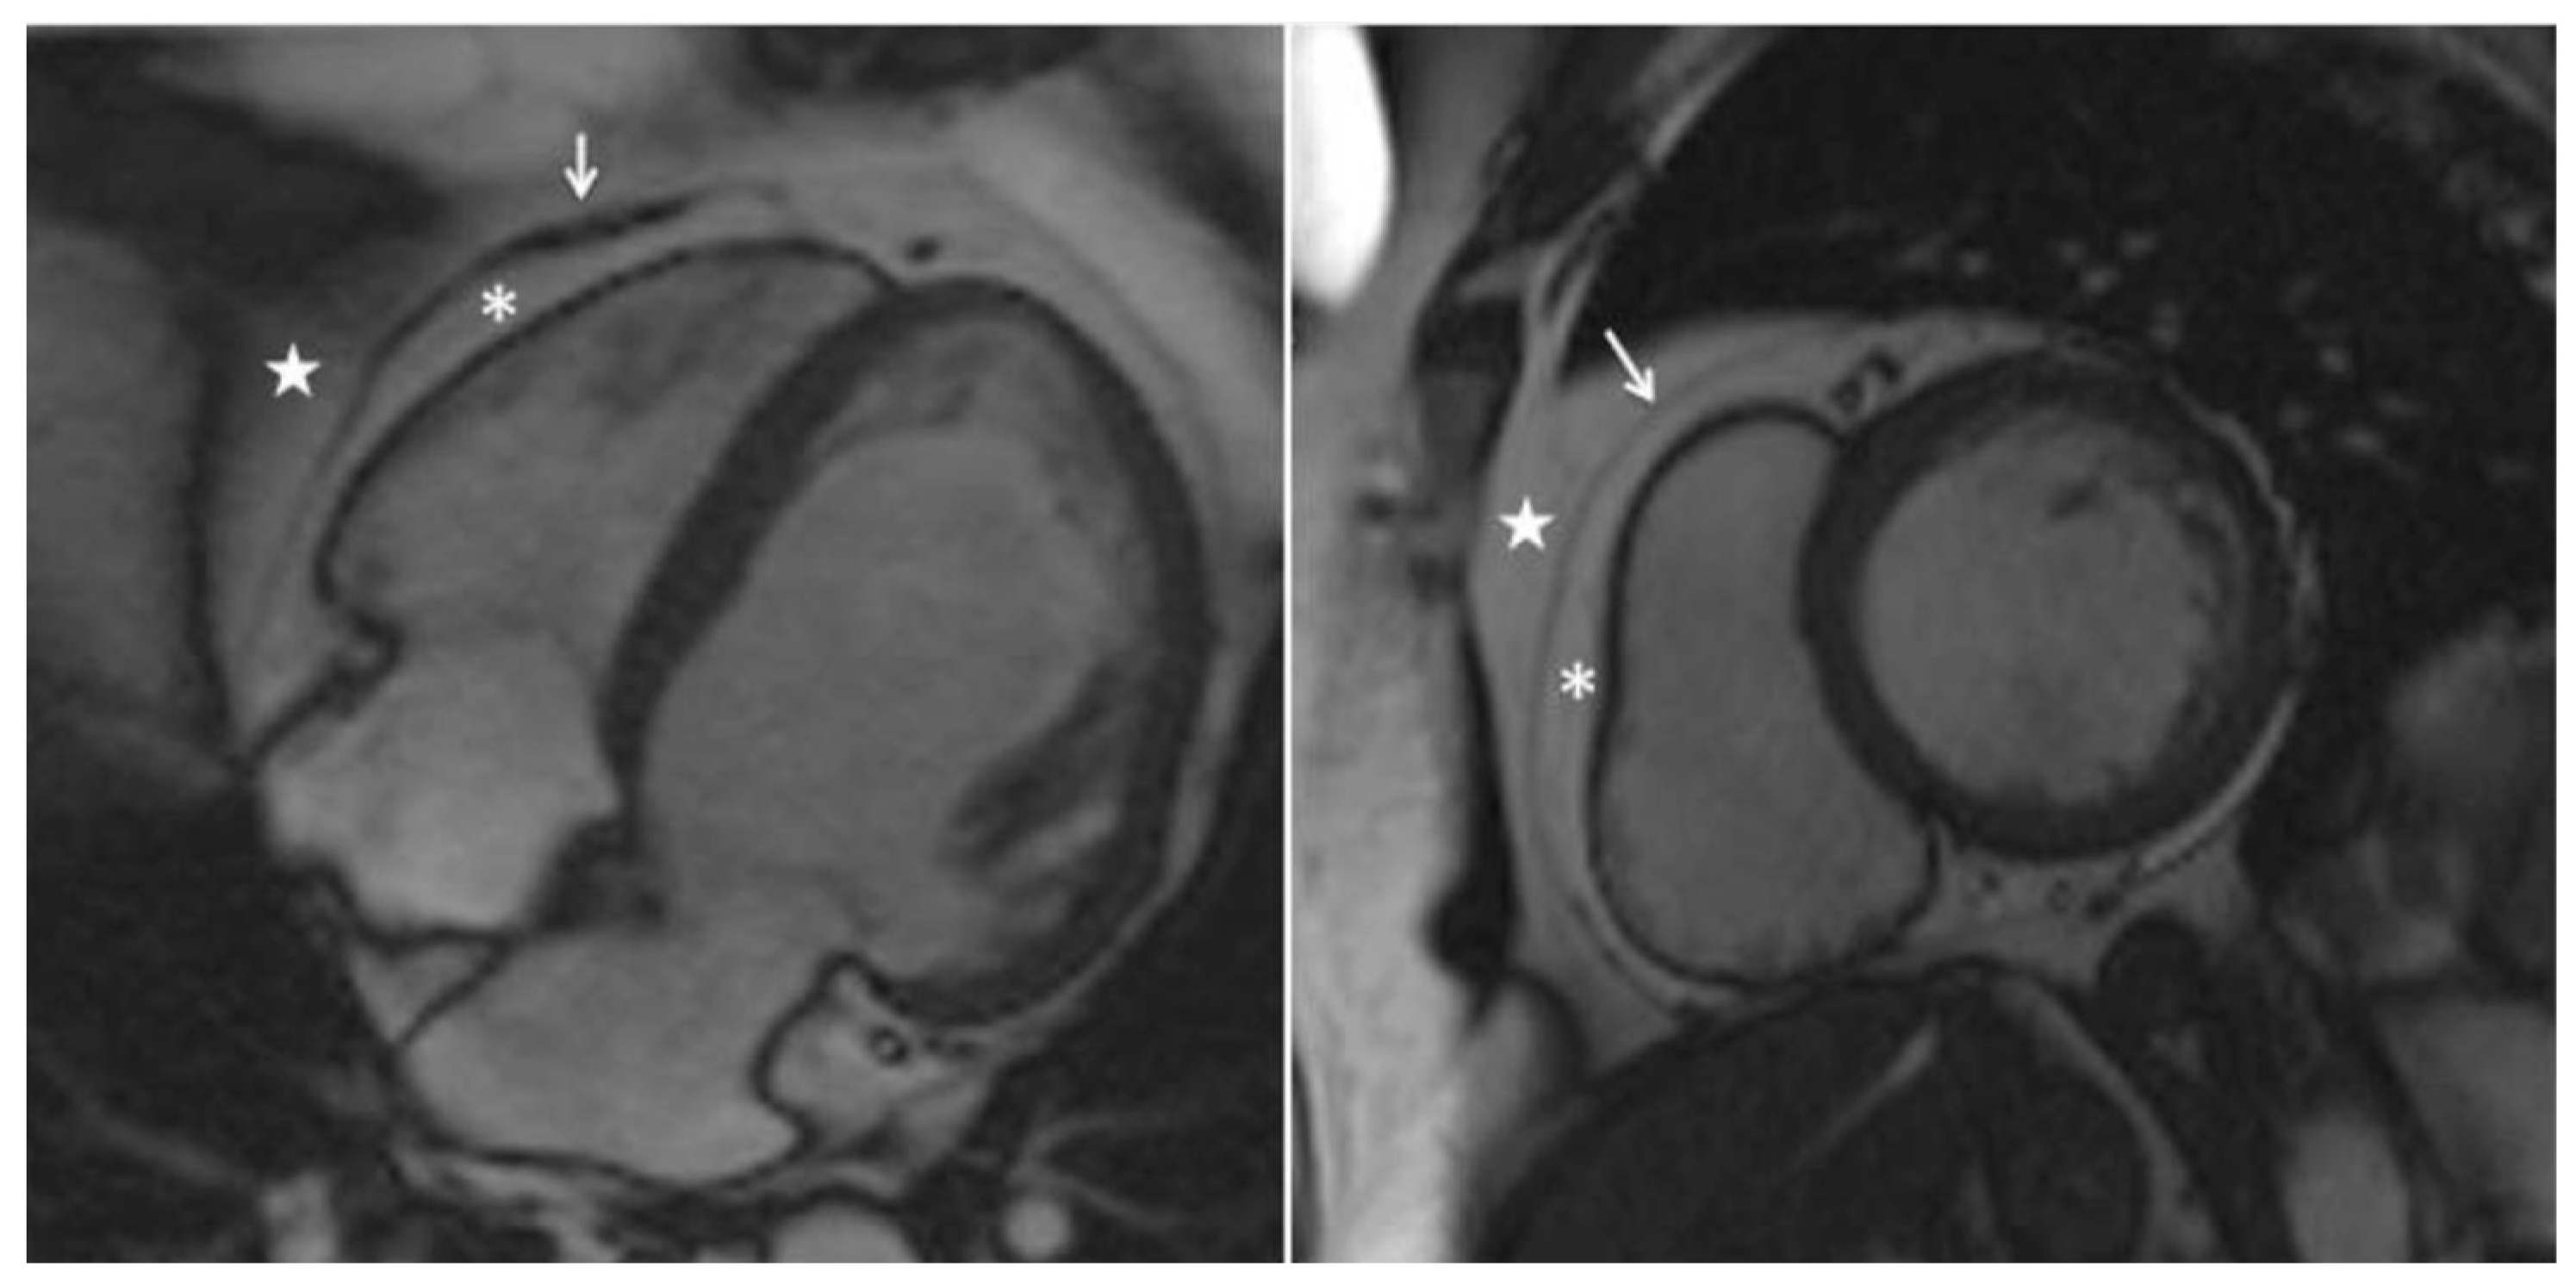

- Daudé P, Ancel P, Confort Gouny S, et al. Deep-Learning Segmentation of Epicardial Adipose Tissue Using Four-Chamber Cardiac Magnetic Resonance Imaging. Diagnostics. 2022;12(1):126. [CrossRef]